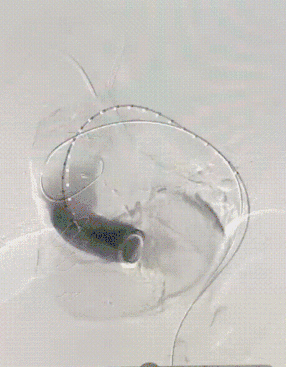

腹主段最终造影

术后随访